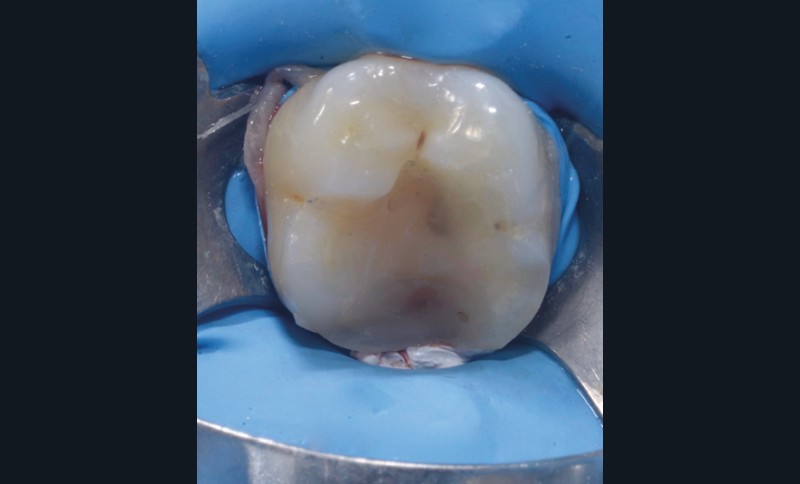

Lors de la préparation d’une cavité pour inlay/onlay, il est fréquent d’être confronté, en fin de nettoyage, à la présence d’une ou plusieurs parois résiduelles dont la résistance mécanique paraît douteuse du fait de leur localisation ou de leur épaisseur. Les parois épaisses (+ de 2 mm) peuvent généralement être conservées (cas clinique 1) et les parois fines (- de 1 mm) doivent généralement être recouvertes. Un inlay (en composite ou en céramique) est alors réalisé. Il doit avoir lui même, au final, une épaisseur globale minimale de 2 mm pour assurer sa résistance mécanique intrinsèque à la mastication. Si un recouvrement cuspidien est indiqué, la réduction occlusale doit donc se faire sur 2 mm de hauteur au minimum [1, 2].

La localisation (type de dent)

Le pronostic clinique semble plus favorable pour les prémolaires que pour les molaires [3-5], car une plus grande résistance est généralement nécessaire pour les parois des molaires. Mais si 75 % des fractures à la mandibule affectent les molaires, et plus particulièrement la première molaire, au maxillaire, les fractures se répartissent équitablement entre le secteur molaire et le secteur prémolaire [6]. L’épaisseur de l’émail, la largeur de la cuspide comme les…